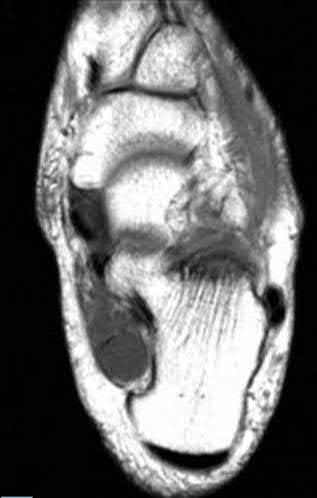

A 64-year-old woman is thrown off a horse, sustaining the injury shown in Figures A and B. She undergoes surgical fixation as seen in Figures C through E. What is the most commonly reported complication of this procedure?

1) Axillary nerve injury

The patient in the scenario has a 2-part proximal humerus fracture treated with a locking plate as seen in Figures A-E. The most common complication with the use of this implant is screw penetration. The terms screw cut out and penetration are often used interchangeably in the literature with cut out appearing more frequently in reports regarding intertrochanteric fractures.

Owsley et al retrospectively reviewed 53 proximal humerus fractures treated with locking plates and the same post-operative protocol. The most common complication was screw cut out or penetration, followed by varus displacement. They concluded that 3 and 4-part fractures in patients over 60 years have a higher incidence of failure.

Agudelo et al retrospectively reviewed 153 patients at a level-one trauma center treated with proximal humerus locking plates, investigating modes of failure for the implant. They determined that varus malreduction (head-shaft angle